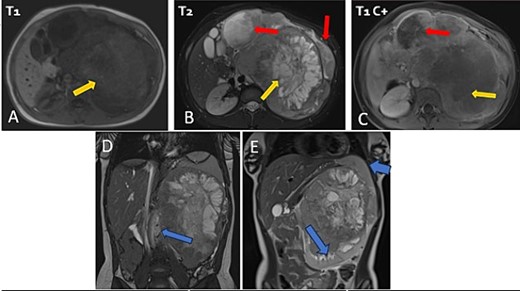

The patient underwent sonography followed by magnetic resonance imaging (MRI), which showed a large lobulated retroperitoneal left tumour measuring 20 × 16 × 14 cm, which was hypointense on T1-weighted and heterogenous on T2-weighted images with necrotic components and contrast-enhancing after Gadolinium administration. This mass invaded the left kidney, causing homolateral pelvicalyceal dilatation (Fig. 1). Routine staging for metastasis showed: lymph nodes and peritoneal carcinomatosis nodules, pulmonary nodules revealed on a thoraco-abdomino-pelvic computed tomography (CT) scans, and secondary-looking osteolytic lesions (Fig. 2) confirmed by scintigraphy.

Abdominal MRI in axial T1 (A), T2 (B), and a T1 fat-saturated post contrast (Gadolinium) sequence (C), coronal T2 (D and E) showing a large retroperitoneal tumour process lateralized to the left, hypointense on T1-weighted, hyperintense, and heterogenous on T2-weighted images with central areas of necrosis and contrast-enhancing after Gadolinium administration. Lymph nodes and peritoneal carcinomatosis nodules are associated. Displacement of the vascular axes (D) and of the spleen of the left kidney responsible for left pelvicalyceal dilation (E).